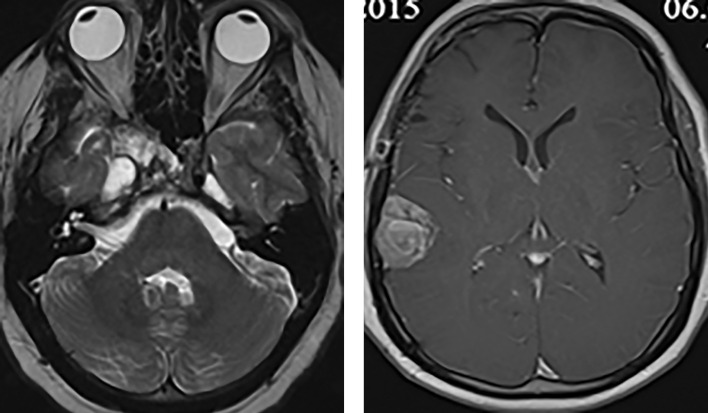

垂体癌(垂体转移性神经内分泌肿瘤)是指已证实有颅脑和/或全身转移的垂体肿瘤。这类肿瘤极为罕见,仅占所有垂体瘤的 0.1%至 0.5%,死亡率很高。在本病例中,一名年轻患者在出现侵袭性复发性分泌催乳素垂体瘤 25 年后被诊断为垂体癌伴颅内转移。标准治疗(转移灶切除、放射治疗、卡麦角林治疗)使病情长期缓解。

Pituitary carcinoma (metastatic neuroendocrine tumor of the pituitary gland) is the pituitary tumor with confirmed craniospinal and/or systemic metastases. These tumors are extremely rare accounting for only 0.1% to 0.5% of all pituitary tumours and are characterized by high mortality. In the presented case, pituitary carcinoma with intracranial metastasis was diagnosed in a young patient 25 years after manifestation of an aggressive recurrent prolactin-secreting pituitary tumor. Standard therapy (removal of metastasis, radiation therapy, cabergoline therapy) resulted in a long-term remission of the disease.